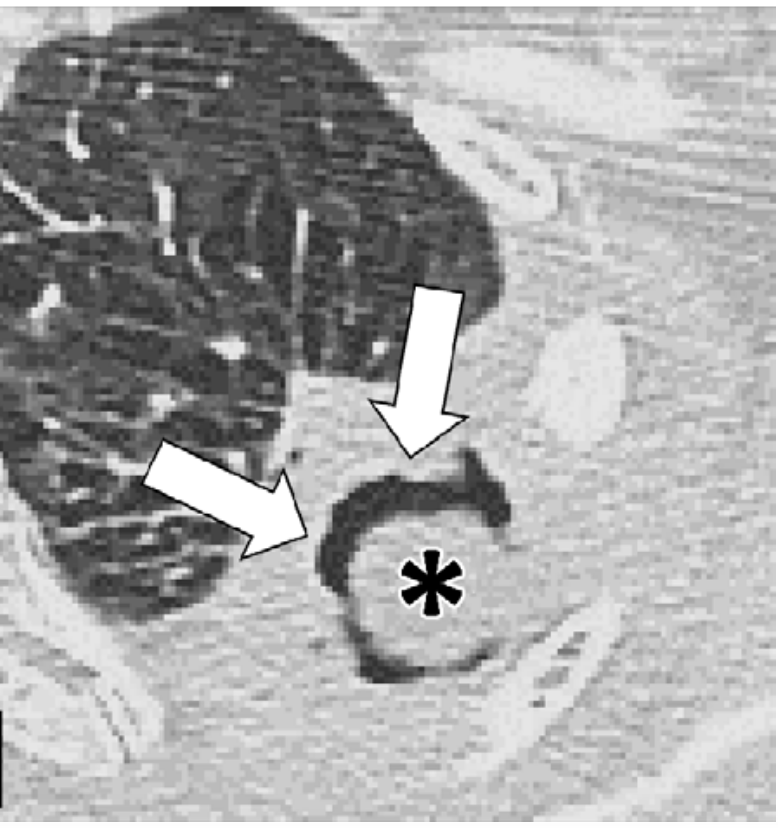

肺曲霉球影像学表现为空洞内的圆形结构,常在团块与空洞内壁之间显示空气新月征(图 2)。曲霉球 CT 可呈现海绵样结构,并可能伴有钙化。曲霉球通常具有移动性,其在空洞内的位置变化可通过让患者采取不同体位(如仰卧位、俯卧位)进行成像来确认(图 3)[1]

图 2. CT 示左上叶原有空洞内出现曲霉球(*),周围呈空气新月征(箭头)[1]